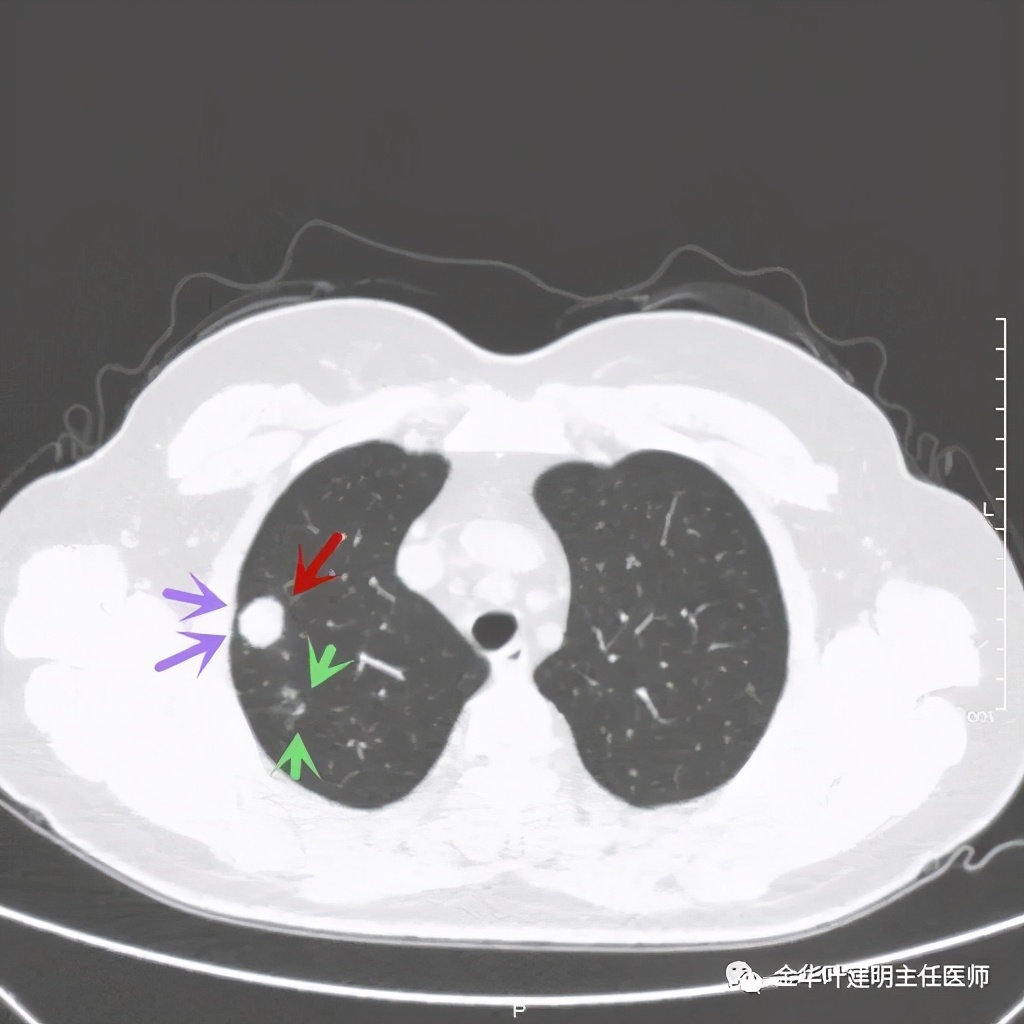

主病灶光滑,旁边有不清爽的小斑点状病灶

紫色箭头示病灶与胸膜很近,但无牵拉凹陷,绿色箭头示附近有微小其他病灶

上图示病灶内侧有个小的空泡

绿色箭头示病粉旁边有卫星灶,而且密度都高,主病灶也是实性

病灶边散在多发微小实性与似磨玻璃的微小结节